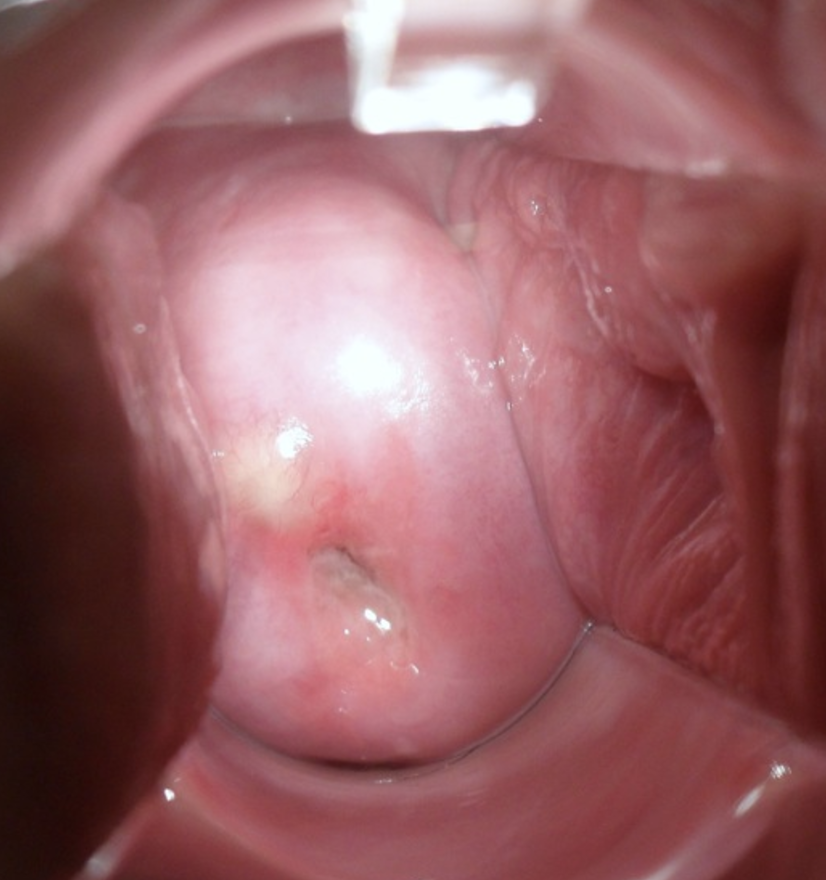

nabothian cyst

benign lesion on cervix at transformation zone

can be seen during cervisitis inflammation, or during metaplasia occuring at SCJ